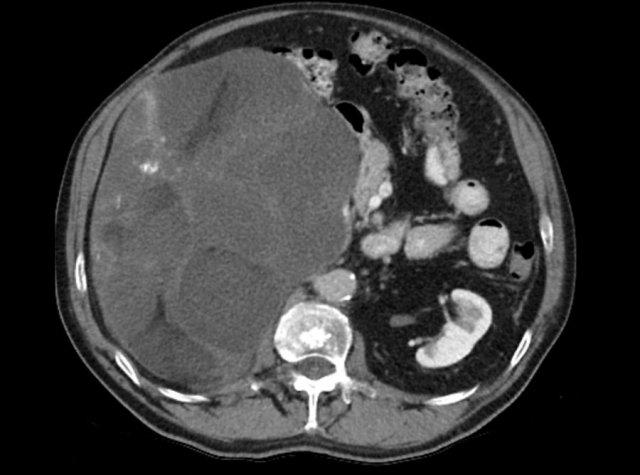

Hình ảnh cho thấy một khối không đồng nhất, bờ không rõ, kích thước lớn hơn 4 cm.

Có vùng trung tâm ngấm thuốc kém, nhiều khả năng là do hoại tử trung tâm.

Trong trường hợp cụ thể này, sinh thiết đã được thực hiện và cho thấy ung thư biểu mô tuyến, có thể xuất phát từ ung thư phổi nguyên phát.

Tuy nhiên, điều đáng ngạc nhiên là phân tích hình ảnh toàn diện, bao gồm cả FDG PET-CT, không phát hiện được khối u nguyên phát.

Hình ảnh cho thấy một tổn thương ngấm thuốc không đồng nhất, bờ tương đối rõ, kích thước 67 mm.

Sau phẫu thuật cắt bỏ, tổn thương được xác định là ung thư biểu mô vỏ thượng thận.

Hình ảnh cho thấy một tổn thương không xác định kích thước lớn với tỷ trọng không đồng nhất và vỏ vôi hóa một phần.

Sinh thiết cho thấy u cơ trơn tuyến thượng thận.

Tổn thương đã được phẫu thuật cắt bỏ.

Đây là tổn thương không xác định, ngấm thuốc không đồng nhất, bờ tương đối rõ.

Tổn thương được xác định là u tủy thượng thận (pheochromocytoma).

Tổn thương tuyến thượng thận ngấm thuốc mạnh kích thước 7 cm với các ổ nang nhỏ.

Tổn thương được phẫu thuật cắt bỏ do kích thước lớn và đặc điểm hình ảnh không xác định.

Kết quả mô bệnh học xác định đây là u tuyến (adenoma).